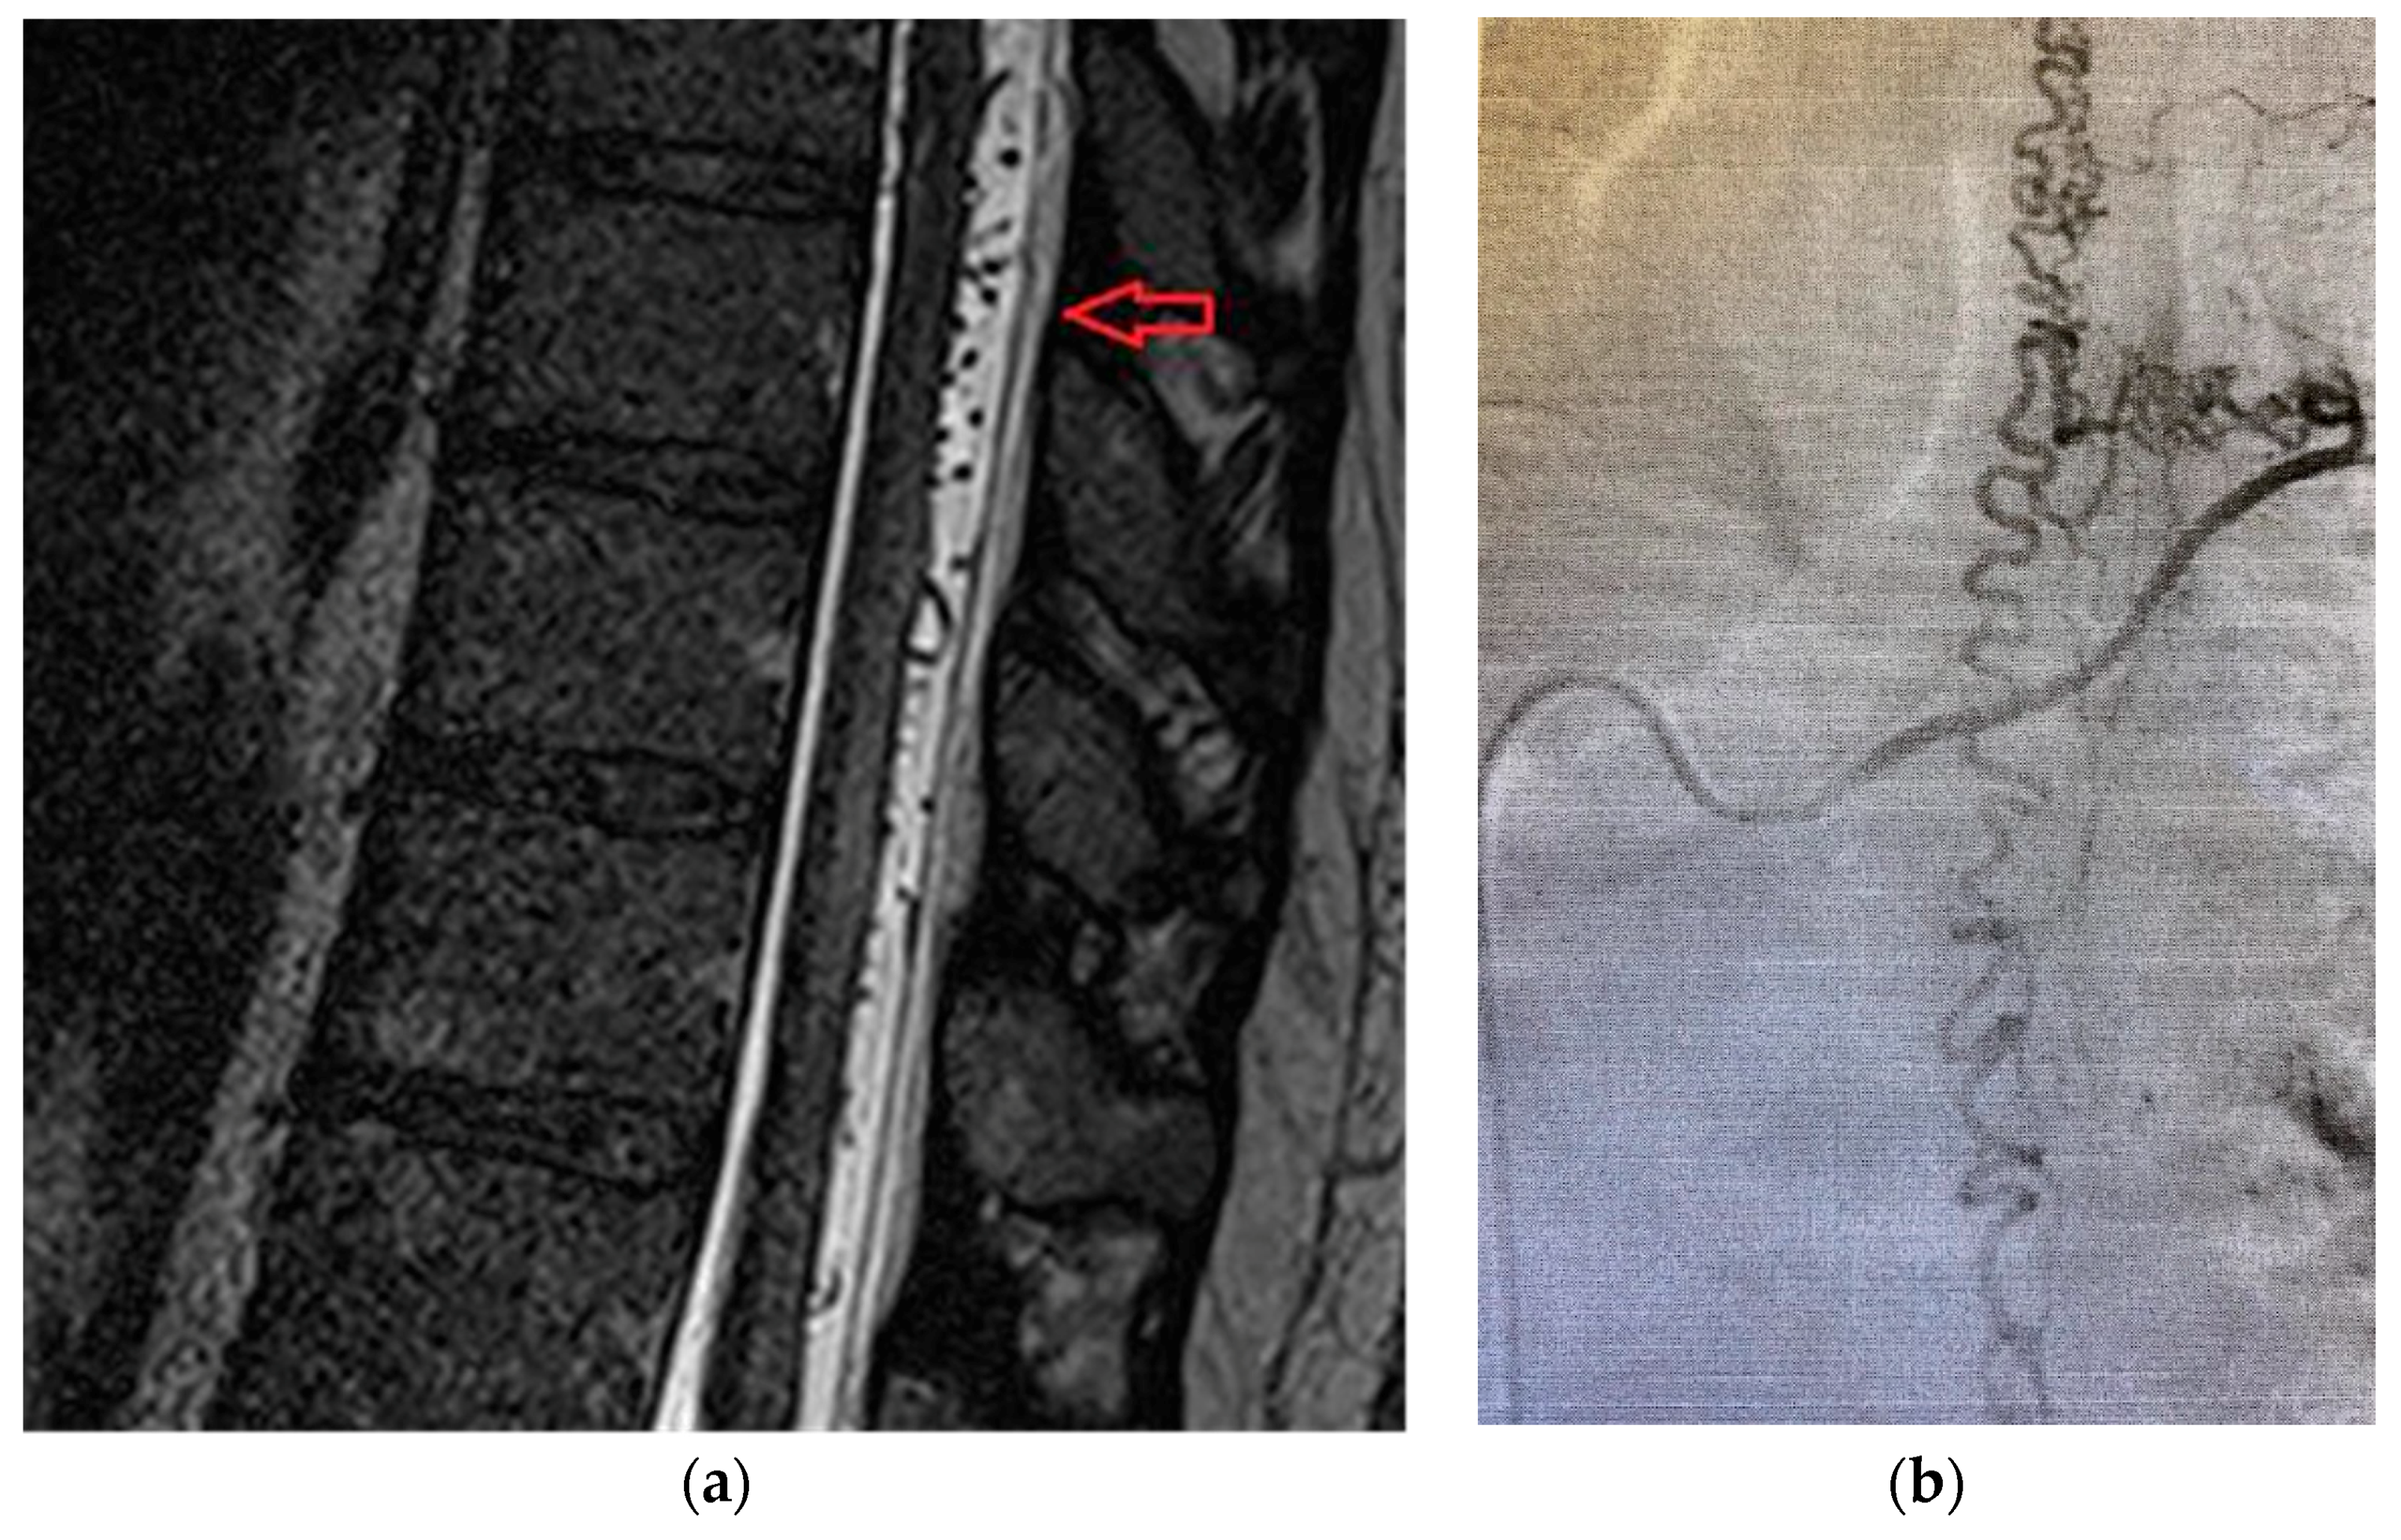

Patient was a 62-year old male, with progressive onset in four months, who presented initial symptoms such as difficulty in climbing stairs, paresthesias and radicular pain in the lower limbs. The symptoms were ascending in time and later patient was paraplegic, with total sensory loss below T2, urinary retention and constipation. Imaging data is available in Figure 4a,b.

Figure 4. (a) MRA shows a “flow voids phenomena” at the dorsal side of the spinal cord below level T2 and multiple zone (T2, T3, T6) with spinal cord edema on T2-weighted sequence. (b) MRA revealed posterior extradural acute hematoma at T2-T8 spinal levels.